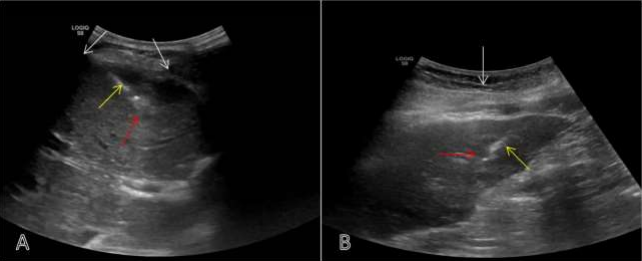

Figure 01: (A) Intercostal Approach – USG guided FNAC of segment IV liver lesion (red arrow). White arrow denoted ribs and yellow arrow FNAC needle. (B) Transabdominal / Sub-xiphoid Approach – USG guided biopsy of segment III liver lesion (red lesion). White arrow denoted anterior abdominal wall and yellow arrow biopsy needle.